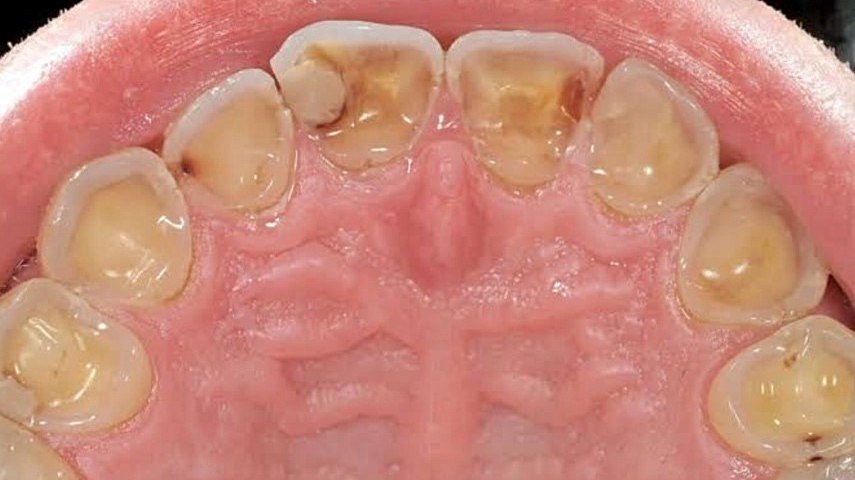

Reflü gibi mide hastalıklarında midenin asidik içeriği sıkça, aslında bulunmaması gereken bir bölge olan özofagus ile temas ediyor. Bu asidite ve midedeki gaz birikimi ağıza ulaştığında dişlerin arka bölgelerinde aşınmalara sebep oluyor.

Aynı senaryoyu anoreksiya/blumia’da sık istifra etmeye bağlı olarak midenin asidik içeriğinin dişlerin arka bölgelerine teması sonucunda da izleyebiliyoruz. Bunu, en yukarıdaki görselde görebilirsiniz.